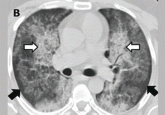

ArticleAlveolar proteinosis: A slow drowning in mudAuthor:Mohammed H. Alshati, MDPublish date: August 1, 2014The patient improved markedly after whole-lung lavage and has had no recurrence at 1 year.Read More